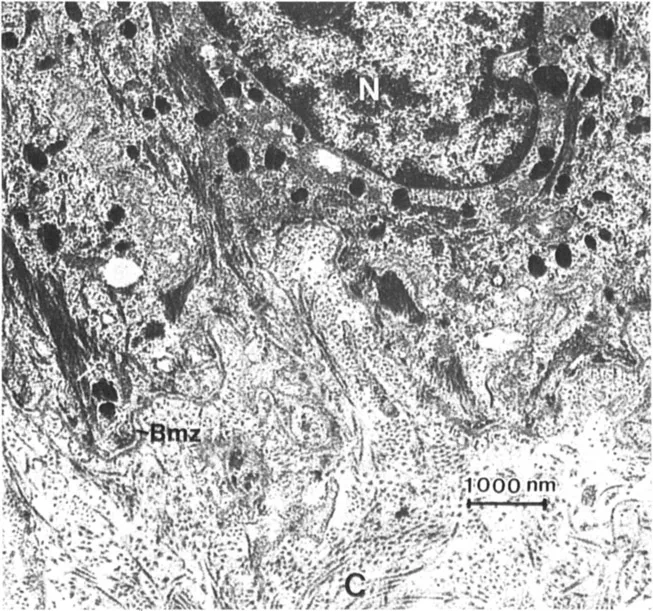

When the ultrastructure of any connective tissue is examined, a large variety of extra-cellular fibrous structures can be identified. For example, Figure 1 illustrates the ultra-structure of human skin dermal-epidermal junction. The cytoplasm and plasma membranes of the basal cells are adjacent to the connective tissue matrix. In this zone, the basal cells are separated from subjacent matrix by a dense, amorphous structure known as the basement membrane or basal lamina. Subjacent to the basement membrane is the connective tissue matrix. This matrix contains a variety of fibrous structures, the most obvious of which are the large, cross-striated fibers showing a 67-nm periodicity. These are the structures first identified as collagens, and they represent the most common fiber form of these molecules. But, in addition to the banded collagen fibers, a fine, reticular network is also visible. Alfco, in this tissue, banded fibers with a centrosymmetric cross-striation can be seen that appear to originate in the lamina densa of the basement membrane and run perpendicularly from the basement membrane into the upper layers of the dermis. These structures, which are common to basement membrane regions of striated epithelial origin, are known as anchoring fibrils (3). Another fibrous structure can be identified between the hemidesmosomes in the plasma membrane of the basal cells and the lamina densa. These fine filamentous structures have been termed anchoring filaments (4). Many of these fibrous elements are believed to be composed of different collagen types. The lamina densa of the basement membrane is clearly collagenous. The fine filamentous feltwork is an aggregate of at least one other collagen type. There is some evidence that the anchoring fibril is a specialized condensation of yet another collagen type (5). The anchoring filament appears not to be collagenous.

Figure 1 Transmission electron micrographs of the dermal-epidermal junction at two magnifications. A variety of fibrous structure are identified: collagen fibers (C); the basement membrane zone (Bmz), which includes the lamina lucida (LI) and the lamina densa (Ld); anchoring fibrils (AF); anchoring filaments (af); and the reticular network (Rn). The nucleus (N) and hemidesmosomes (H) are also identified.

Figure 1 illustrates several important points, (a) The extracellular matrix is made from a variety of collagen types, (b) The fibrous elements in connective tissues have different fiber forms, and these fiber forms can be attributed to different organizational patterns of the various collagen types, (c) Many of these fiber forms have restricted distributions, such as the basal lamina and the anchoring fibrils.